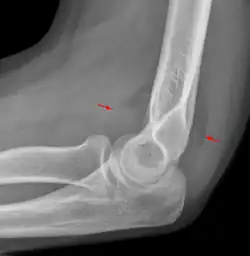

A normal anterior fat pad in a non-fractured arm.